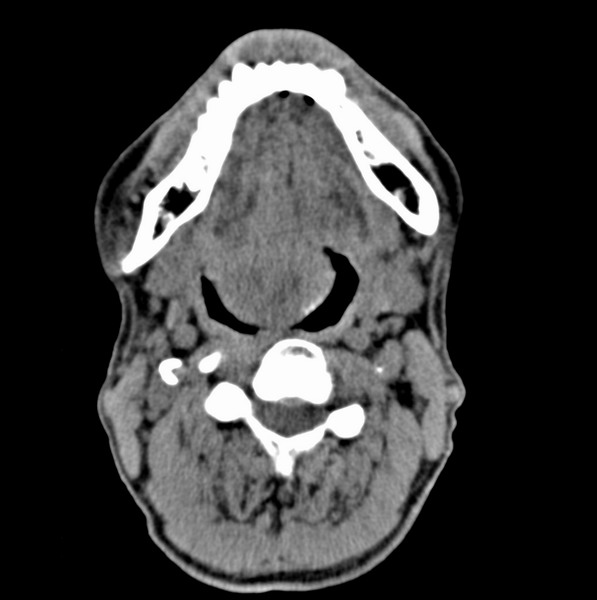

标题: CT19620:舌根肿物

男、60、舌根肿物。

舌垂直肌和横肌影处肿块影,边缘不规则,咽腭扁桃体及舌下间隙脂肪影消失,病变侵及口咽。

考虑-----舌根癌

舌跟软组织肿块,较大有坏死,钙化。结合年龄一般是恶性肿瘤。

舌根部较大软组织肿块,其内见坏死低密度区及钙化影;考虑舌根癌可能。